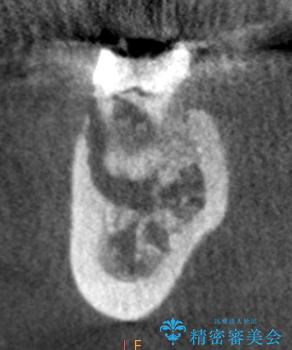

治療途中、マイクロスコープでも根管が追えないほど狭く細くなった根管へと変性しており根管の拡大形成が難しい状況でした。

CTを撮影し少しづつ丁寧に根管を探索することで無事根管再治療を行い、症状がなくなりました。